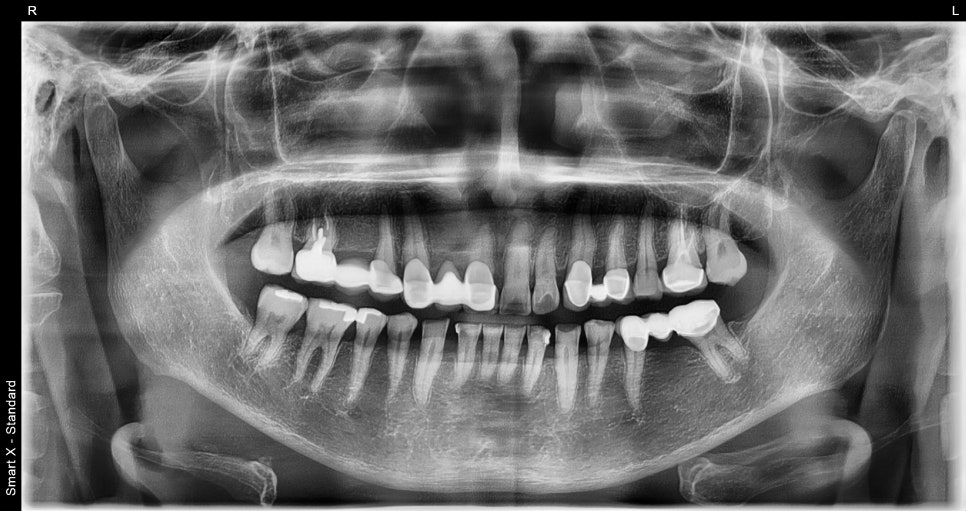

처음 내원 하셨을 때 파노라마 X-ray

➤초진 진단 소견

앞니 심미 보철과 어금니 임플란트 치료를 계획하기 전, 환자분의 초기 상태를 확인한 모습입니다.

치아 배열, 상실 부위, 기존 보철 상태 등을 종합적으로 진단한 결과, 다음과 같은 치료 계획을 안내드렸습니다:

오른쪽 아래 어금니 부위(#45~47): 오래된 브릿지를 제거하고 #45 47 크라운 새로 제작하는 것을 권장드렸으며, #46 빈자리는 기존 브릿지 대신 임플란트 1개 식립을 안내드렸습니다.

앞니 부위(#11): 치경부 마모가 심하여 추가적인 보철 치료가 필요한 상태였습니다.

아래 앞니 부위(#43, #42): 치아 사이의 공간이 커져 크라운을 이용한 심미적 개선을 계획했습니다.